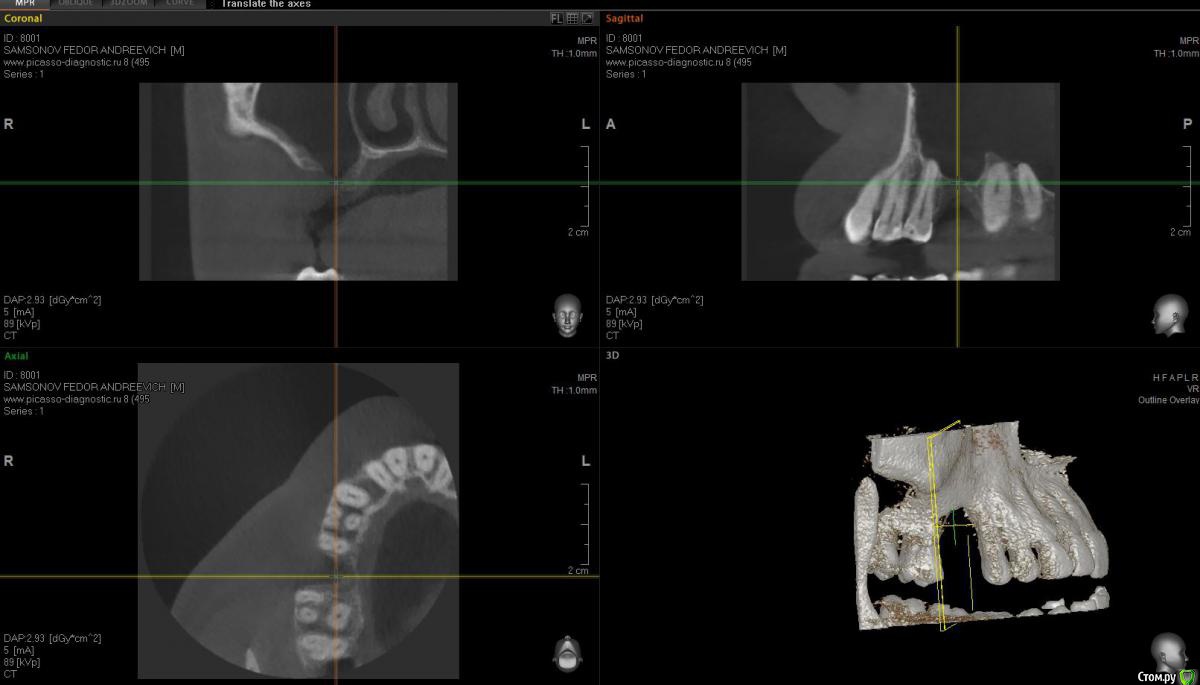

Федор С Опубликовано 1 февраля, 2018 Поделиться Опубликовано 1 февраля, 2018 Здравствуйте!Подскажите, пожалуйста, как лучше поступить в моей ситуации. Предыстория такова: из-за некачественно сделанной в свое время коронки, под верхней правой шестеркой образовалась киста. После грубого удаления зуба, образовалась большая дырка.Вопрос в следующем: ставить мост или попытаться нарастить костную ткань и поставить имплант?Сам больше склоняюсь к имплантации, но смущает, что дефект очень большой, в объеме около одно кубического см.Фото прикладываю, так же на всякий случай прикладываю ссылку на КТ (КТ делал в "Пикассо") КТ только папка DATA с диска - http://fayloobmennik.cloud/7187773Если не будет открываться, КТ весь диск целиком - http://fayloobmennik.cloud/7187772 Заранее спасибо! Ссылка на комментарий

Bier Опубликовано 1 февраля, 2018 Поделиться Опубликовано 1 февраля, 2018 грамотный хирург нарастит там кость. вот очень похожий на ваш случай: http://forum.stom.ru/topic/35126-sostoianie-posle-udaleniia-s-oas-kak-byt-upd-sdelal/ Ссылка на комментарий

Bier Опубликовано 1 февраля, 2018 Поделиться Опубликовано 1 февраля, 2018 вот так закончился случай. Ссылка на комментарий